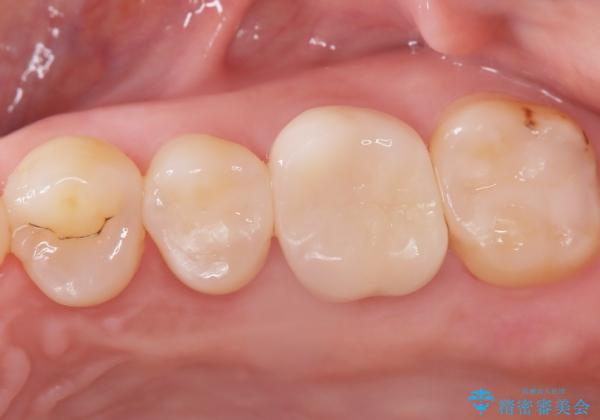

2回で完了した奥歯のセラミック修復

今回の治療では、虫歯の大きさや深さに応じて、異なるセラミック修復法を適用しました。

比較的軽度な虫歯には、セラミックインレー(詰め物)で対応し、健全な歯質を最大限に残しました。

進行した虫歯や歯の強度が低下している歯には、セラミッククラウン(被せ物)を選択し、歯全体を保護することで破折を防ぎました。

短期間での治療を可能にしつつ、天然歯と見分けがつかない審美性と、長期的に安定する機能性を兼ね備えたセラミック修復を実現しました。